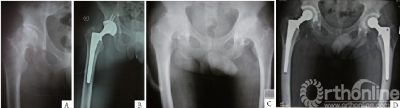

A组手术切口长6.0~10.5(平均7.4) cm,平均术中出血量387.6(140.0~1000.0) mL,平均术后引流量143.1(60.0~375.0) mL,平均输血量77.6(0~ 400.0) mL,手术平均时间84.6(63.0~130.0) min, 术后影像学髋臼杯外展角平均41.6°(38.0°~57.0°)。B 组手术切口长约15.0~23.0( 平均20.0) cm , 平均术中出血513.1(210.0~1350.0) mL ,平均术后引流量152.3(70.0~520.0) mL ,平均输血量142.2(0~800.0) mL ,手术平均时间84.0(71.0~115.0) min ,术后影像学髋臼杯外展角平均42.3°(37.0°~54.0°) 。两组比较,手术切口长度( t = -33.105 ,P <0.05) 、术中出血量(t=-2.485,P<0.05),差异具有统计学意义(表2; 图1,2)。

图2 后外侧小切口人工全髋关节置换术前术后影像学资料。A:单侧股骨头缺血性坏死;B:单侧非骨水泥型人工全髋关节置换术后;C:双侧髋关节骨关节炎;D:双侧骨水泥型人工全髋关节置换术后。